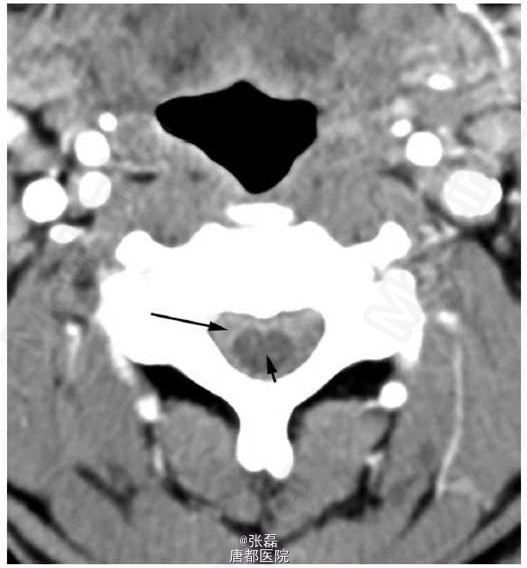

患者男性,51岁,因活动中突发后背疼痛前来急诊科。

神志清楚,定向正常,痛苦面容,生命体征为:体温 35.7°C,心率 86 次 / 分,血压 127/77 mmHg,呼吸 18 次 / 分,血氧饱和度 98%(未吸氧)。体格检查示大汗,包括心脏与神经系统查体在内均未见异常。首次治疗予以患者大剂量静脉用麻醉药物及止吐药物,但疼痛未缓解。

急诊行 T1-T5 椎板切除术与减压术。术后诊断为蛛网膜下腔出血肿块在髓内扩大,导致脊髓受压以及神经系统功能障碍。病理检查提示为血肿。随后,患者接受了脊髓血管造影进一步评估可能的出血源。血管造影未发现动静脉畸形或其他血管畸形。